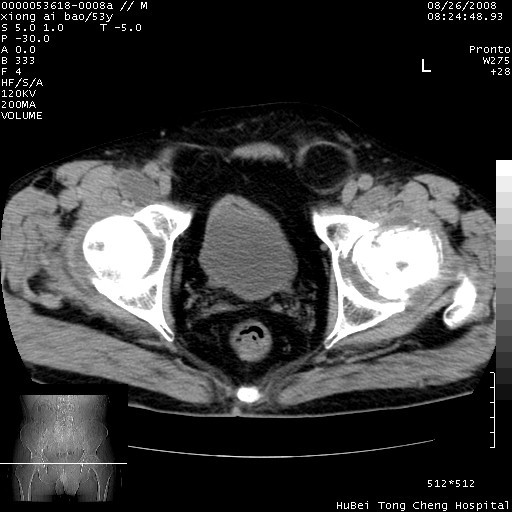

标题: CT15583:M,53Y。请老师指教分析骨盆及其他病变。 [打印本页]

标题: CT15583:M,53Y。请老师指教分析骨盆及其他病变。

股骨头坏死/腹股沟疝。

双侧股骨头无菌坏死,左侧腹股沟斜疝。

非常典型病例,双侧股骨头坏死伴双髋关节周围软组织肿胀,左腹股沟疝。

双侧股骨头坏死伴双髋关节周围软组织肿胀,左腹股沟疝。

双侧骨股头无菌性坏死,左侧腹股沟疝

双侧髋关节肿胀明显,感觉还不能排除结核。

考虑双侧髋关节结核,左侧腹股沟疝